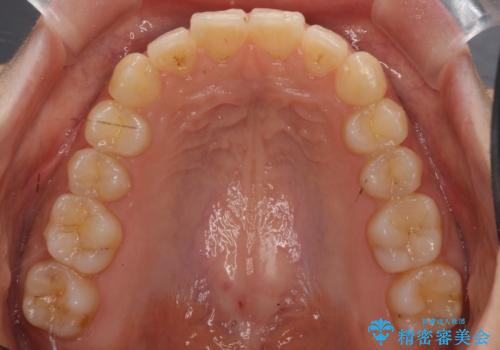

犬歯のねじれ 下の歯のがたがた インビザラインで

- 右上の犬歯のねじれ、下の歯のがたつきを主訴に来院。

インビザラインで歯を抜かずに並べました。

初回:上顎16ステージ 下顎22ステージ

リファインメント: 上顎23ステージ 下顎20ステージ